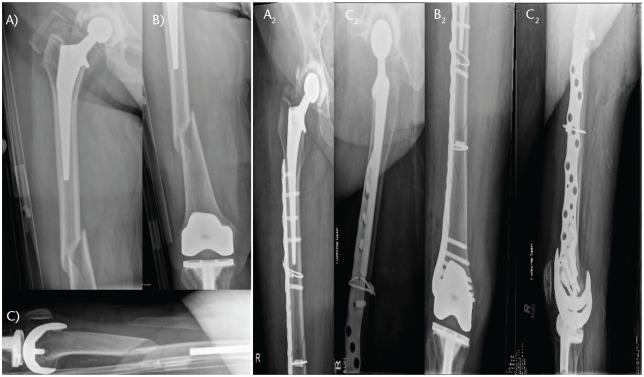

The Vancouver classification is still a useful tool of communication and stratification of periprosthetic fractures, but besides the three parameters it considers, clinicians should also assess additional factors.Combined advanced trauma and arthroplasty skills must be available in departments managing these complex injuries.Preoperative confirmation of the THA (total hip arthroplasty) stability is sometimes challenging. The most reliable method remains intraoperative assessment during surgical exploration of the hip joint.Certain B1 fractures will benefit from revision surgery, whilst some B2 fractures can be effectively managed with osteosynthesis, especially in frail patients.Less invasive osteosynthesis, balanced plate-bone constructs, composite implant solutions, together with an appropriate reduction of the limb axis, rotation and length are critical for a successful fixation and uneventful fracture healing. Cite this article: 2021;6:75-92. DOI: 10.1302/2058-5241.6.200050.

温哥华分类仍然是假体周围骨折沟通和分层的有用工具,但除了它所考虑的三个参数外,临床医生还应评估其他因素。处理这些复杂损伤的科室必须具备综合的高级创伤和关节置换技术。全髋关节置换术(THA)术前稳定性的确认有时具有挑战性。最可靠的方法仍然是在髋关节手术探查期间进行术中评估。某些B1型骨折将受益于翻修手术,而一些B2型骨折可以通过接骨术有效处理,尤其是在体弱患者中。微创接骨术、平衡的钢板-骨结构、复合植入物解决方案,以及适当矫正肢体轴线、旋转和长度,对于成功固定和骨折顺利愈合至关重要。引用本文:2021;6:75-92。DOI:10.1302/2058-5241.6.200050。